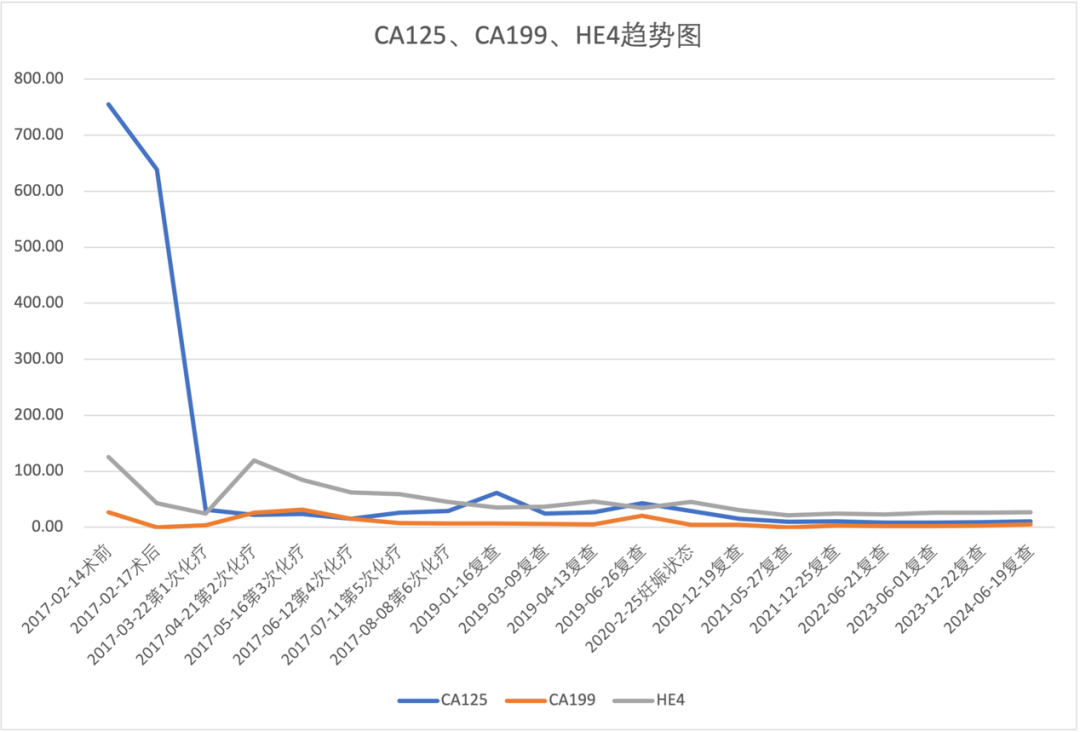

【现病史】 【既往史】 【婚育史】 【月经史】 【家族史】 直系亲属无类似疾病史。父亲高血压病史,否认其他家族遗传性疾病史。 【入院后的检查检验】 ✦经腹部+阴道联合超声(2017-02-15,我院): ✦肿瘤指标: 【入院诊断】 2、子宫颈炎 3、不孕症 中青年女性,已婚未育,因“B超发现盆腔包块半年余”就诊。患者右侧附件区可见一个混合回声,形态不规则,边界尚清晰,内部回声不均匀,大小约98mm*70mm*64mm,其内可见不规则液性回声,附壁可见低回声突起,大小约38mm*15mm*39mm,其内可见点状彩色血流信号可见彩色血流信号。患者既往有卵巢囊肿切除术史。肿瘤指标糖类抗原CA125:755.5U/mL,人附睾蛋白4:124.9pmol/L。 经腹双侧卵巢肿瘤剥除术+大网膜切除+阑尾切除术+腹主动脉旁淋巴结取样术+盆腹腔多点腹膜活检术+盆腹腔转移肿瘤结节切除术 【术中探查见】 【术中快速病理】 【术后常规病理】 【术后基因检测结果】 【术后诊断】 2、卵巢交界性浆液性乳头状瘤Ⅲc期 3、右侧卵巢巧囊术后 4、腹主动脉旁淋巴结内异症 【术后治疗】 TC化疗6L疗程。化疗期间予诺雷德3.6mg皮下注射。 【术后妊娠】 ✦产科病史: 入院检查:宫高:34cm,腹围:104cm,估计胎儿大小:3500g,胎方位RSA,FHR:144次/分,先露:臀。 辅助检查:B超示:双顶径:93mm,腹周径:307mm,股骨长:68mm,羊水指数:89mm,胎盘附着于子宫后壁,Ⅲ-级,考虑胎儿脐带绕颈一周可能,LSA位。 ✦肿瘤指标: ✦MRI(2020-02-25,我院): ✦手术方案: 于2020-02-26在全麻下行子宫下段剖宫产术+次广泛性子宫切除术+双侧附件切除术+盆腔淋巴结清扫术+腹主动脉旁淋巴结清扫术(肾静脉水平)+盆腹腔转移肿瘤结节切除术+盆腹腔多点腹膜活检术+部分网膜切除术 ✦分娩记录: 手托臀娩出一女婴,体重2850克,评分10-10分 ✦术中快速: (左卵巢)交界性浆液性乳头状囊腺瘤,部分呈微乳头型,伴上皮内癌,待常规多取材除外有无浸润。 ✦术后常规: 患者术后每隔半年规律复查至今,复查内容包括肿瘤指标(CA125、CA199、HE4)、生化全套检验及B超检查,均未见明显异常。 延展讨论 1、手术方案的选择 卵巢交界性肿瘤相对于卵巢肿瘤而言恶性程度较低,复发率低且复发较晚,患者生存期延长,死亡率较低。近年来女性卵巢交界性肿瘤的发病年龄趋于年轻化。在临床调研中显示有50%的患者确诊时<40岁。由于BOTs患者多为育龄期女性,对生育功能的保留是治疗过程中应重点考虑的因素之一。目前保留生育功能手术术式有单侧肿瘤剔除术、单侧附件切除术、双侧肿瘤剔除术(BOC)和单侧附件切除术+对侧肿瘤剔除术(UAC),分期不是绝对禁忌证。此外,BOT易复发,常见高危因素有FIGO分期、手术方式和组织学类型等。浆液型、晚期、微乳头和双侧肿瘤与高复发率相关;单侧附件切除术预后总体优于肿瘤剔除类手术。对于强烈要求保留生育功能的患者需要充分评估肿瘤特性、做好术前告知,谨慎选择术式,术后规律随访。 由于卵巢交界性肿瘤一般分化良好,其代谢活性近似于良性肿瘤,缺乏对化疗药物的敏感性或耐药性,故对于早期患者和术后无残留病灶的患者不建议立即进行辅助性化疗,而应积极定期随访。 2、术后辅助生殖技术 研究表明卵巢交界性肿瘤实行保留生育功能手术对后续不孕症行体外受精、胚胎移植的妊娠结局无显著不良影响。BOTs患者实施辅助生殖技术(assisted reproductive technology,ART)的时机十分重要,大部分观点认为应当在术后至少1-2年再尝试ART但考虑到ART治疗的间隔时间过长可能对于女性卵巢储备功能有较高的要求,术后的妊娠应当在评估了肿瘤复发风险和预后的情况下尽快进行,在术后半年至1年内尝试妊娠。而对于术前术后检测卵巢功能出现下降,无或低自然受孕机会的患者应缩短ART的时间间隔。对于术后病理提示肿瘤有微乳头或间质浸润等情况者,应尽早或在术后半年至一年内开始尝试妊娠。 3、妊娠时机的选择 本案例中患者于化疗结束后半年开始积极备孕,行IVF失败后自然受孕,并于腹腔镜双侧卵巢肿瘤剥除术后2年妊娠。对于有生育需求的患者,妊娠时机的选择也十分重要,原则上应避开复发高峰期,可在术后6-12个月内尝试妊娠;术后选择化疗的患者应在停用化疗药物6-12个月后。还应继续关注其卵巢功能及激素水平,在孕早期及时补充黄体酮保胎,以期达到良好的妊娠预后。

甲胎蛋白:2.531μg/L,癌胚抗原<0.50ng/mL,糖类抗原CA125:755.5U/mL,糖类抗原CA199:26.58U/mL,人附睾蛋白4:124.9pmol/L。

糖类抗原CA125:28.90U/mL,甲胎蛋白:255.78μg/L,人附睾蛋白4:45.20pmol/L,癌胚抗原:0.58ng/mL,糖类抗原CA199:4.10U/mL。